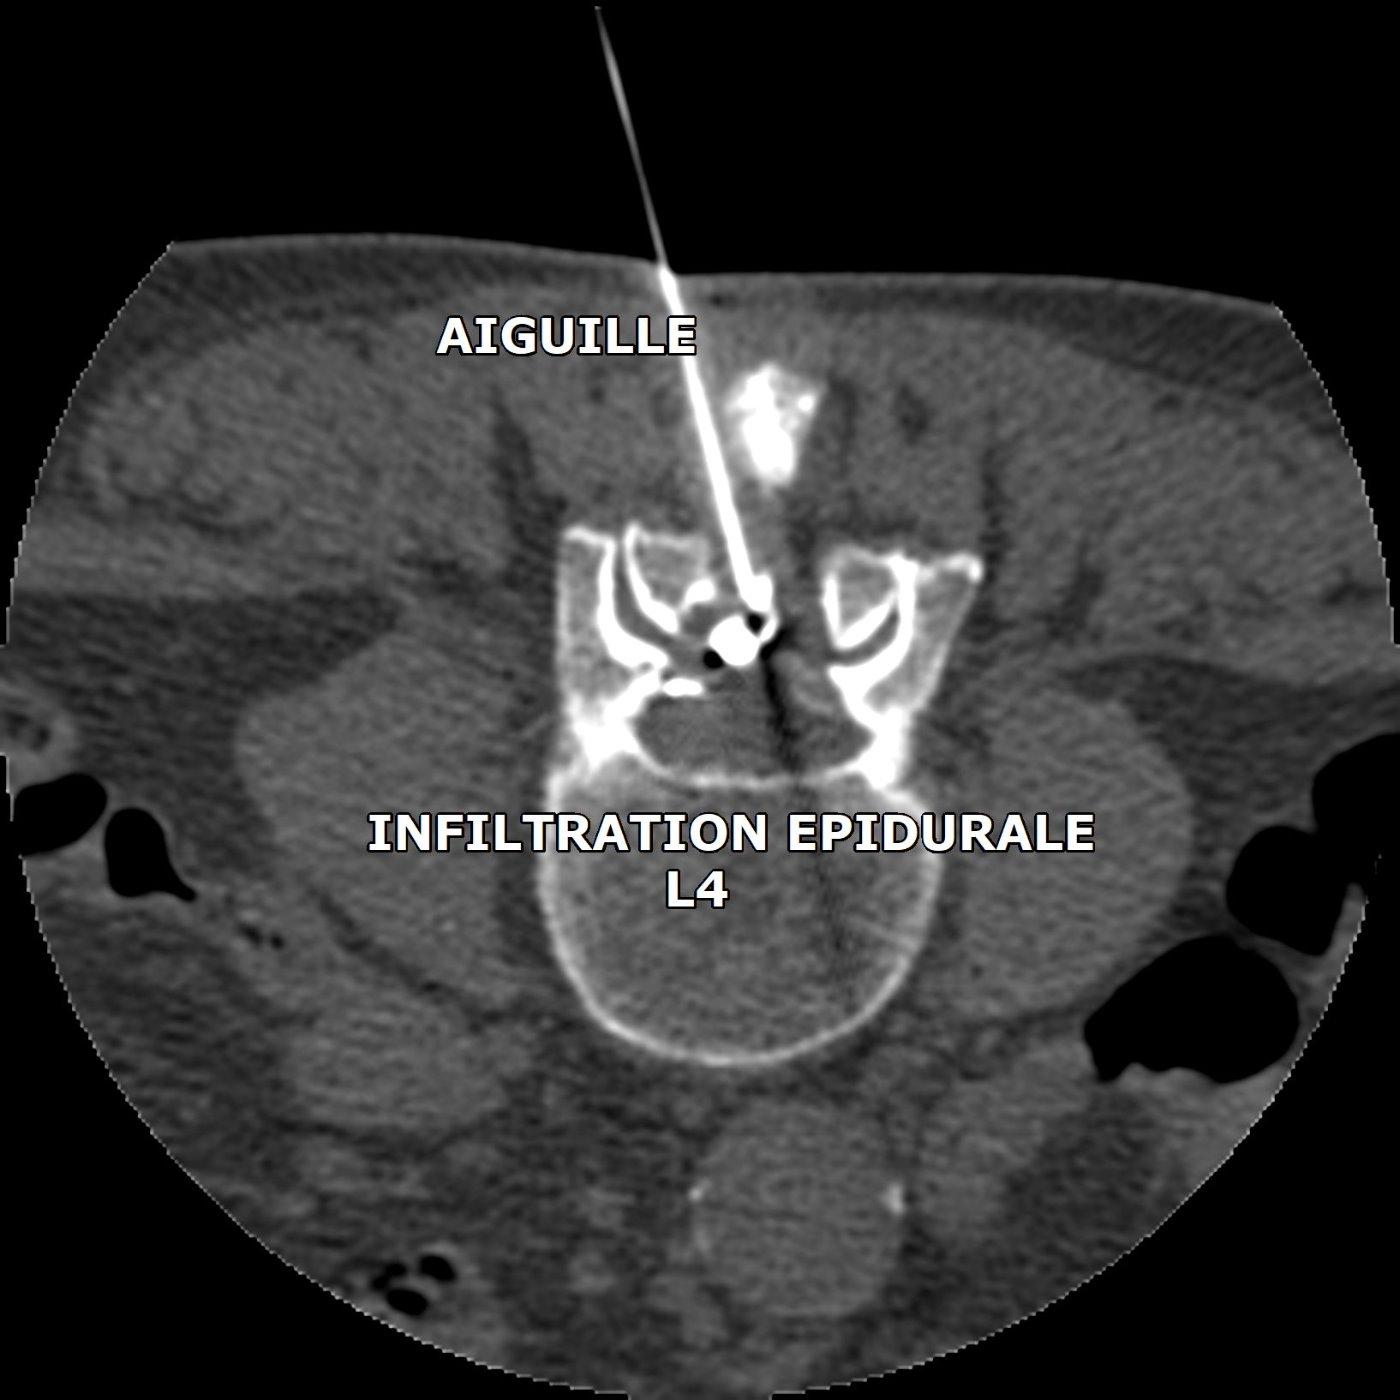

INFILTRATION LOMBAIRE POUR HERNIE DISCALE

le contrôle scanner montre l'extrémité de l'aiguille en place et la diffusion du produit de contraste dans l'espace épidural

Lorsqu'une douleur de "sciatique" ou une cruralgie est provoquée par une hernie discale lombaire, et que la douleur résiste à un traitement médical maximal, le médecin peut proposer la réalisation d'une infiltration lombaire, c'est à dire une injection de corticoïdes dans l'espace épidural.

Nous réalisons cette procédure sous guidage radiographique ou scanner, patient allongé sur le ventre.

La durée de l'intervention est courte, une vingtaine de minutes en comptant l'installation. Après l'infiltration, le patient est installé en position semiallongeé dans une salle au calme.

Un repos doit être observé pendant les 48 heures suivant l'infiltration.

L'efficacité de l'injection s'installe dans les 8 à 15 jours qui suivent l'infiltration.